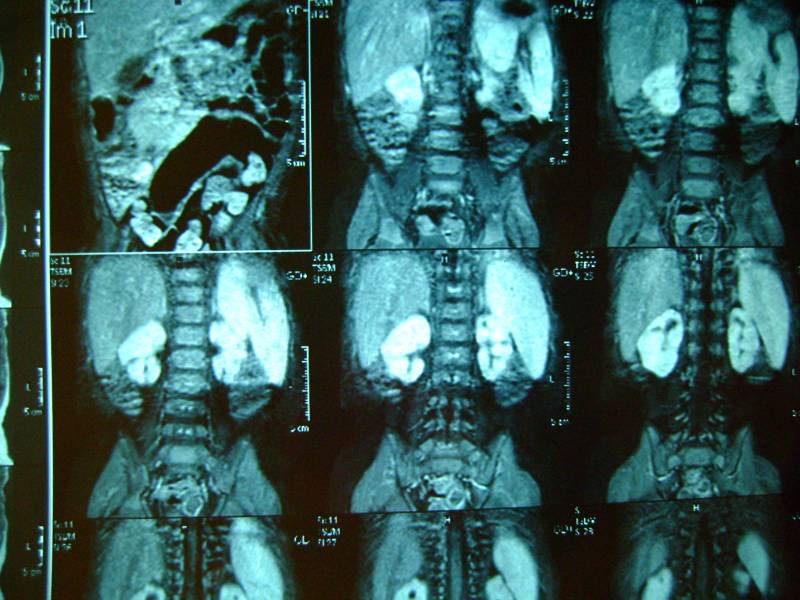

добавляем фото